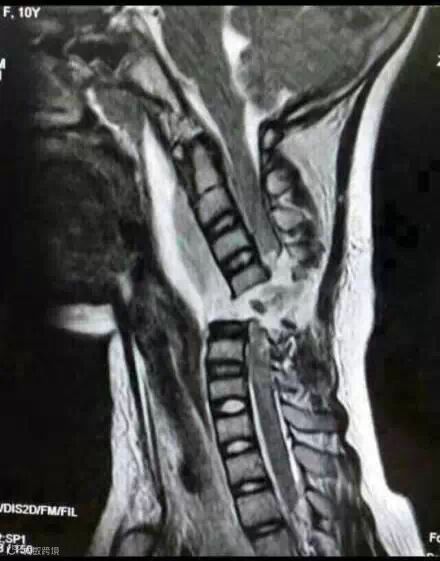

微信朋友圈,很多人都在为这位10岁的小姑娘祈祷。这就是她颈椎完全断裂的图片。

12月2日下午,她戴着长围巾乘坐电动车时,长围巾被车轮绞住。在惯性作用下,小青的脖子被紧紧勒住,电动车停下后,她感觉自己不能动了,而且呼吸也变得非常困难。经过手术,小青终于脱离危险,但由于脊柱断裂,小青已全身瘫痪。同时,意外还影响到了肌肉,小青已不能自主呼吸,目前只能通过呼吸机辅助呼吸。